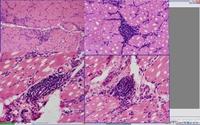

3. 實驗室檢查 ①血清t3、t4、ft3、ft4有不同程度增高。②肌電圖呈肌源性損害特徵。③肌肉活檢。光鏡下可見肌纖維粗細不等、少數肌纖維萎縮變性、橫紋消失、肌膜核增多等。電鏡下可見局限性肌原纖維變性、線粒體異常、脂滴增加、肌膜下糖原累積等。